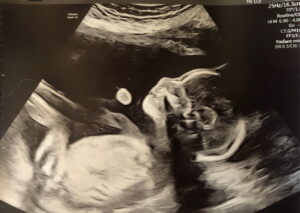

We are currently 29 weeks, 7 months along and both baby and mother are healthy and moving along as we should be. It has been a beautiful experience all around and we commend Dr Monteith for dedicating his life to making other families dreams come true!